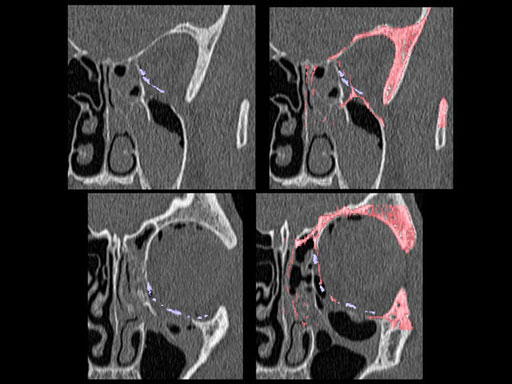

Furthermore, as orbital floor fractures are quite frequently associated with medial wall fractures; anatomic restoration especially in the transition zone between both wall is a demanding procedure. As described by B. Hammer, the orbital floor has an initial shallow convex section behind the rim, then inclines upward behind the globe, and inclines upward to meet the medial wall, creating a distinct bulge behind the globe. These convex curves of the medial wall and floor create a postbulbar constriction of the orbital cavity, which must be reconstructed when the orbit is rebuilt following fractures. Treatment is directed at precise anatomical reconstruction of orbital shape and volume in order to restore the correct position of the eye. To provide surgeons with an adequate implant that addresses the requirements of two wall acute orbital fractures or for secondary reconstruction of enophthalmos and dystopia, a new series of preformed orbital plates was developed for the new orbital matrix system.

Unlike the existing two-dimensional mesh implants, the geometry of the new preformed plates will be adequate to match the individual anatomic situation of the patient in almost any case. However, the mesh parts can be individually adjusted if necessary. In these cases the solid part in the central posterior area needs to remain untouched. Areas of the orbit that do not require a bridging can be spared out by trimming the implant along the designated cutting lines in the height of the medial wall and/or length of the orbital floor area. The lateral anterior part of the plate is intentionally pre-bent higher than the orbital rim anatomy to allow free plate movement during plate positioning.

The Preformed Orbital Plates are indicated for trauma repair and reconstruction of fractures of the orbital floor, medial orbital wall or combined fractures of floor and medial wall. It should be noted that in three-wall fractures where the lateral wall is also involved, a second orbital implant, ( i. e. the mesh plate) must be used in addition to the pre-formed orbital plate.

30 year old male patient with fracture of left orbital floor and medial wall.

Provided by Dr Dr Marc C Metzger, Freiburg, Germany.